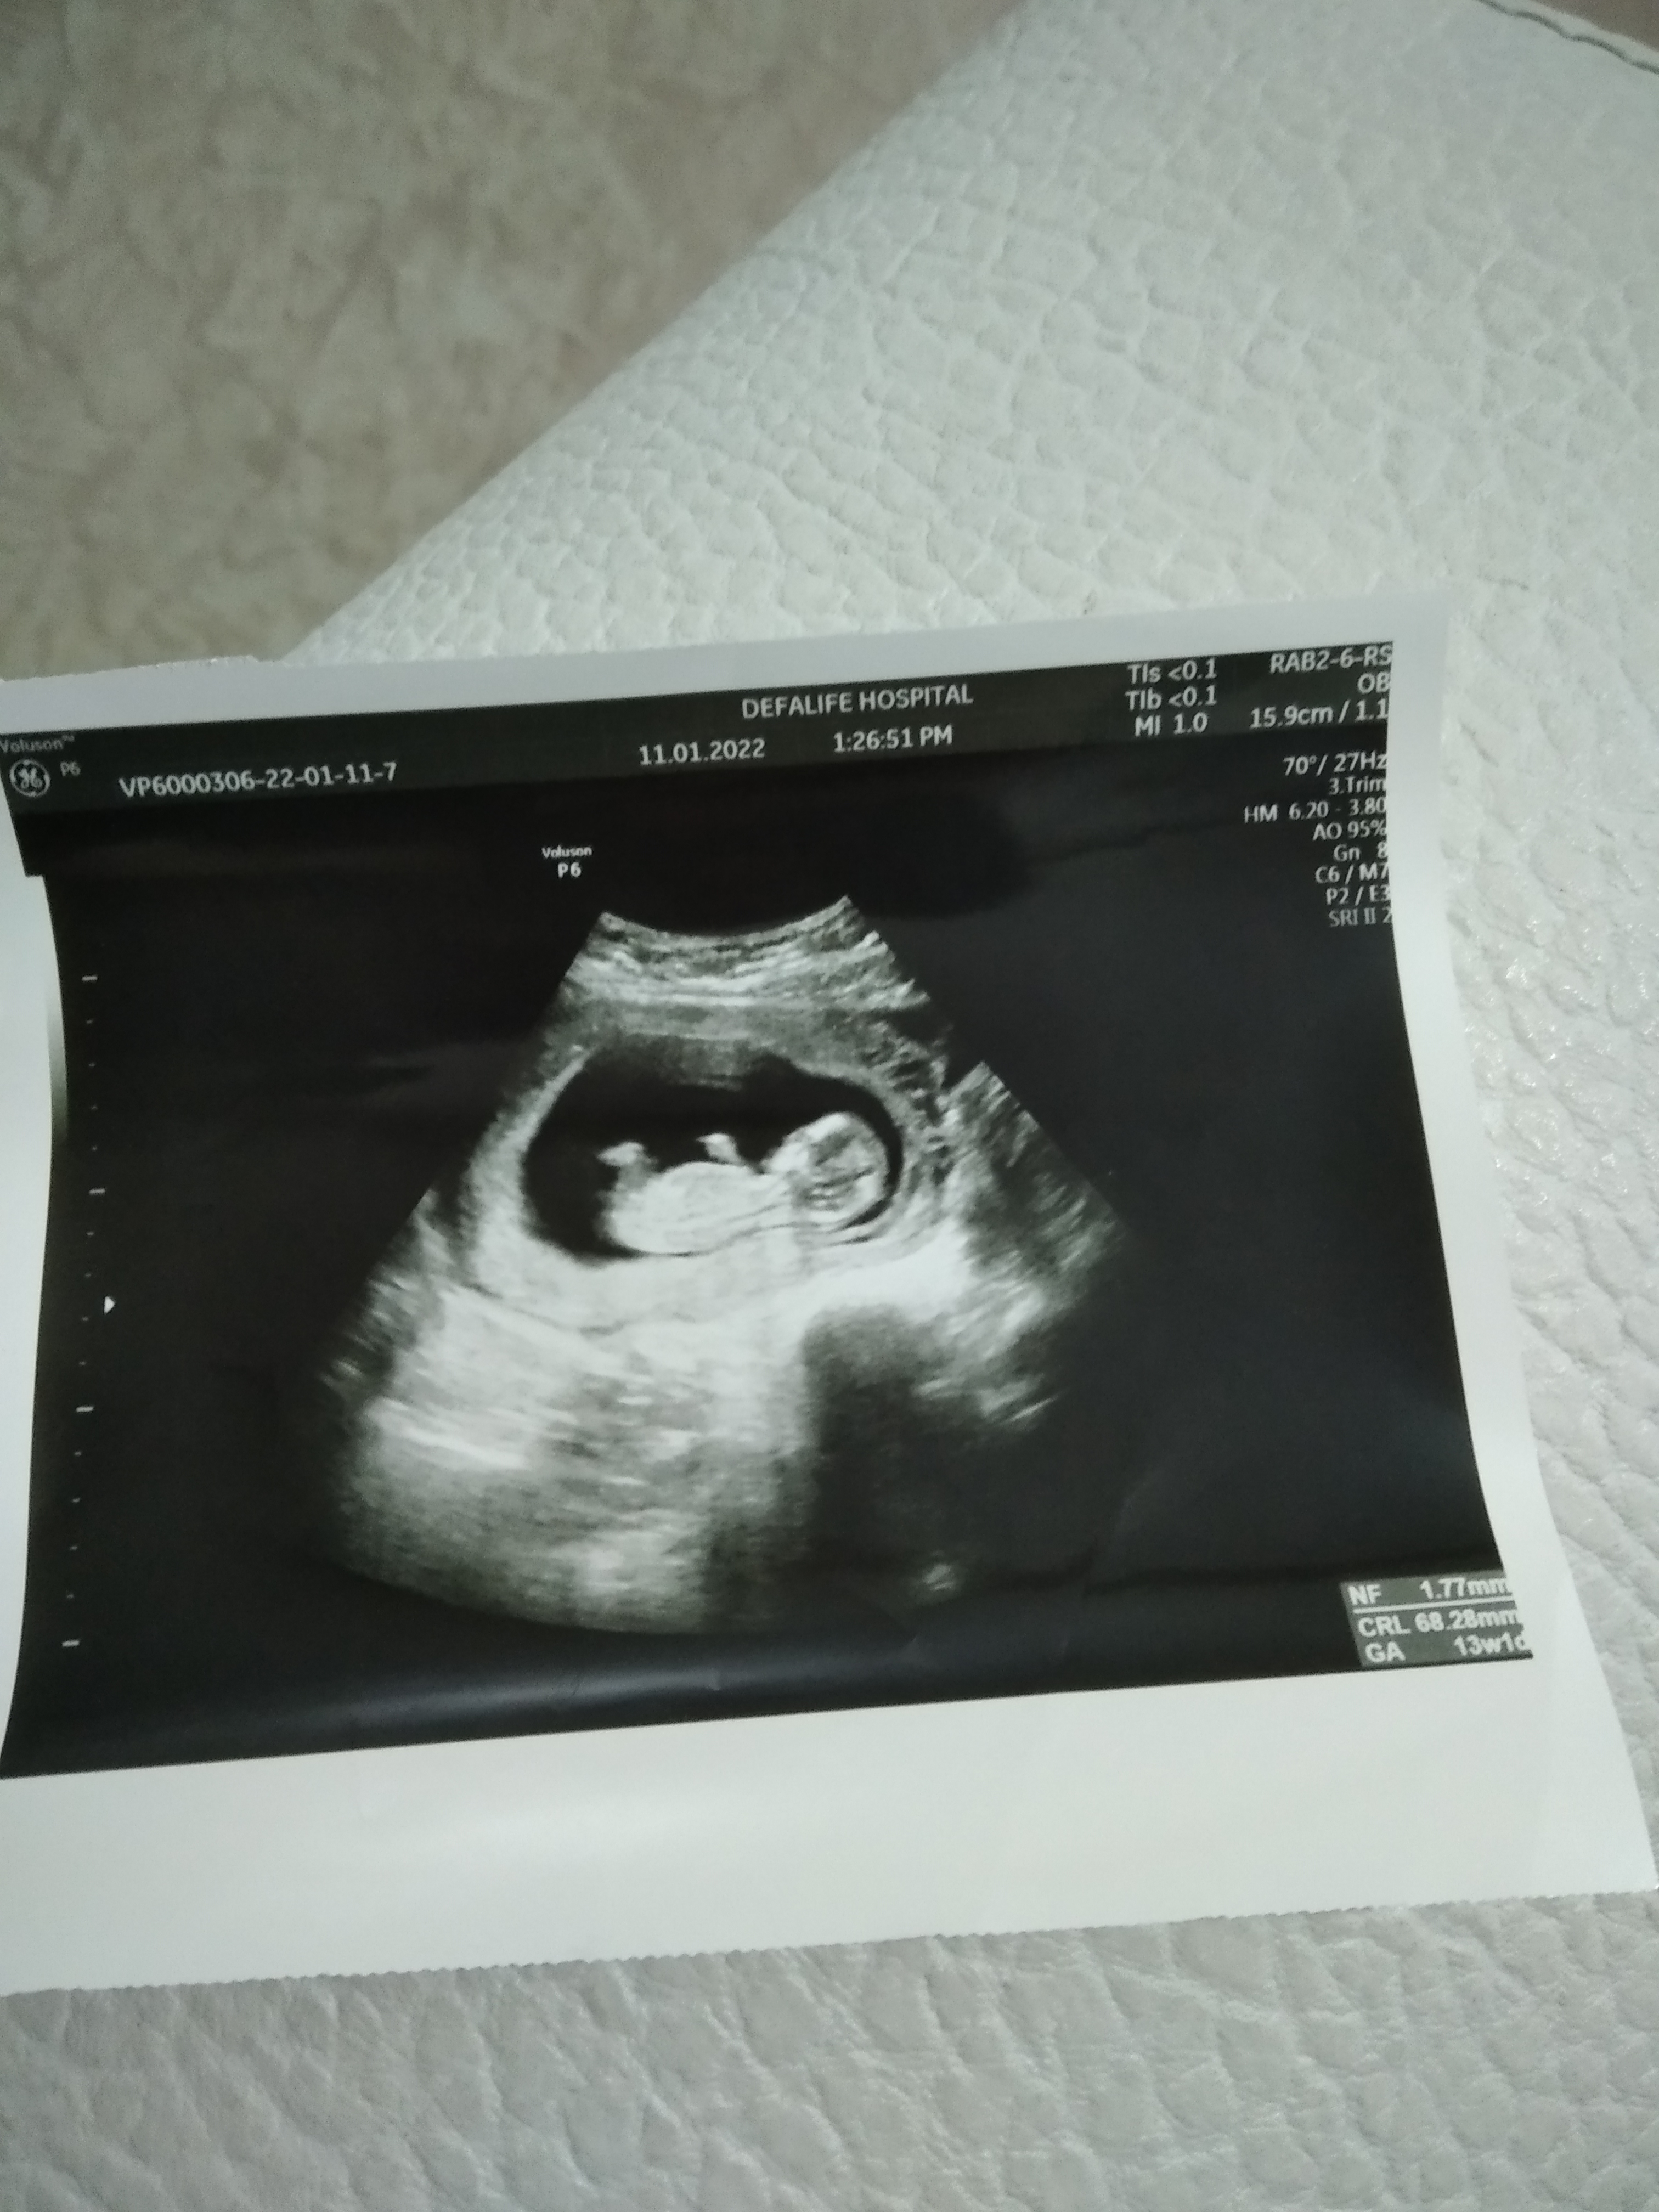

Net olmamakla birlikte ilgili bölgedeki çıkıntıya baktığımda kız gibi görünüyor. Rabbim hayırlısını nasip etsin. Bu tahmin yüzde yüz değildir bilginiz olsun 🙂

Canım. Benim bebiseme de bakar mısın 12+1Selamlar, Ultrason sonucuna göre cinsiyet tahmini var tabiki NUB TEORİSİNE GÖRE CİNSİYET başlıklı konumuzdan resimleri nasıl atacağınız ifade edilmiştir. Hemen konuda aşağıda yer alan özellikle cinsiyet belirlemede olması gereken çıkıntıların çıktısının olması gerekiyor. Bu resimlerin büyüğü var ise gönderin bize ya da linkini verdiğimiz konuya bakarak kendiniz de tahminde bulunabilirsiniz.

Vallahi ben uzman değilim ve Gaybı geleceği olacağı ancak Allah bilir ha illa yüzde verin diyor iseniz %52 kız diyelim![]()